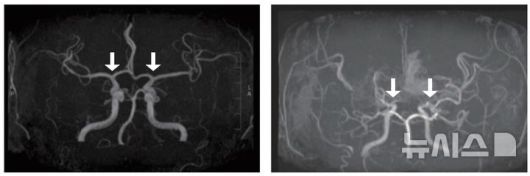

[서울=뉴시스] 사진 왼쪽부터 정상 및 모야모야병 환자의 뇌혈관. (사진= 서울대병원 제공) |

모야모야병은 뇌로 혈액을 공급하는 혈관이 원인 없이 점차 좁아지는 만성 진행성 뇌혈관질환이다. 10세 전후 소아와 40세 전후 성인에서 주로 발병하며, 부작용으로는 뇌혈관이 막히거나 파열되는 허혈성·출혈성 뇌졸중이 있다.